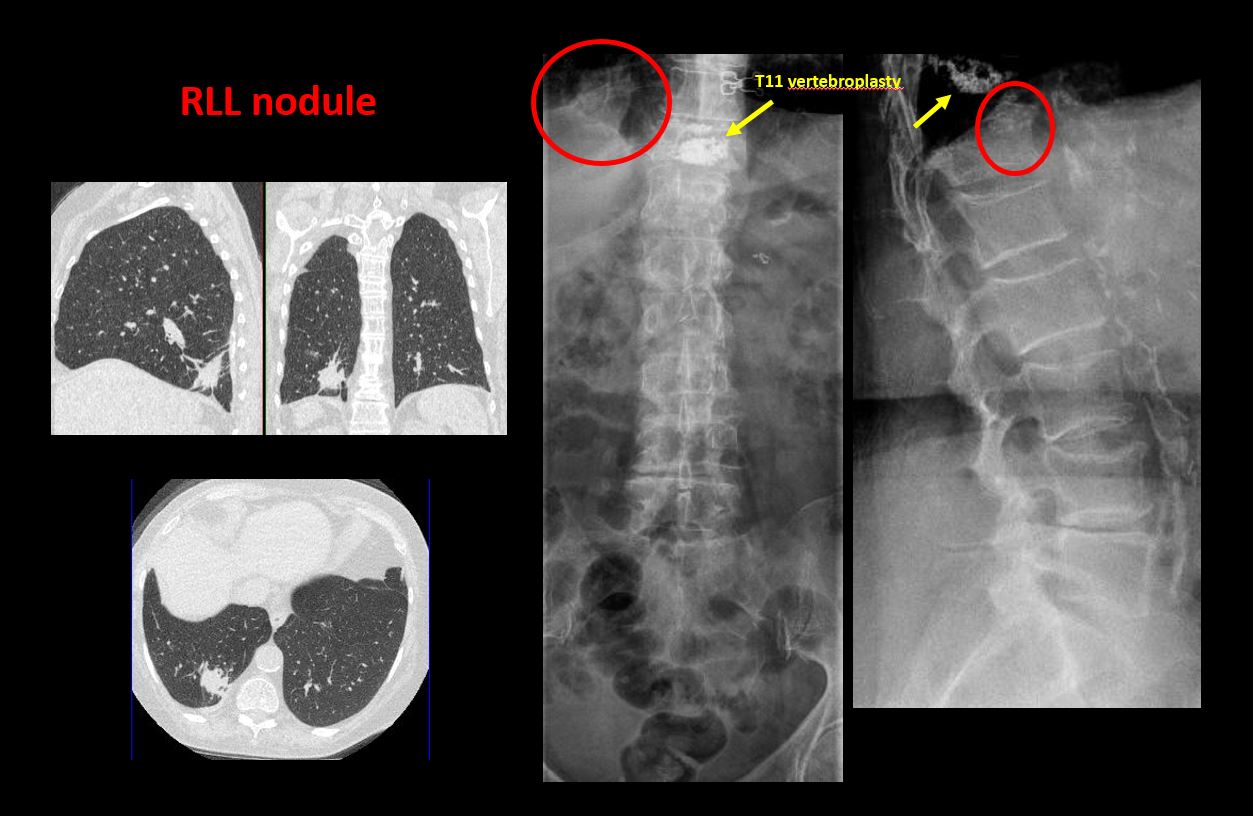

Info Images Findings Impression Reco/Acuity Case Images View Images / Launch Visage Case Notes History 28 yo male involved in an MVC. Exam frontal and cross table lateral views of the lumbosacral spine Prior Study none Dicom View Reference Material

Section 1 Submit Findings CB1239 Findings Technique The thoracolumbar junction and/or the lumbosacral junction is/are not entirely included on the exam. Yes No The exam is over or under penetrated. Yes No The exam is limited by overlying structures, bones or soft tissues, patient positioning, support devices, or motion. Yes No Prevertebral and paravertebral soft tissues The prevertebral or paravertebral soft tissues are abnormal. Yes No Spinal alignment The vertebral bodies are abnormally aligned. Yes No The anterior and posterior vertebral body lines are abnormal or interrupted. Yes No The visualized spinous processes are malaligned or distracted on the AP and/or lateral view(s). Yes No There is reversal or straightening of the normal lordosis or scoliosis of the lumbar spine. Yes No Vertebral bodies, posterior elements and included sacral segments There are more or less than the expected 5 non rib-bearing vertebral bodies. Yes No There is a transitional motion segment at the lumbosacral junction (sacralization of L5 or lumbarization of S1). Yes No There is a fracture or distraction of a vertebral body, transverse or spinous process, or other posterior element. Yes No There is anterior wedging and/or compression of a vertebral body or end plate. Yes No There is an end plate avulsion or other fracture. Yes No There is displacement of a fracture fragment into the soft tissues or spinal canal. Yes No There is lucency or defect of the pars interarticularis from spondylolysis. Yes No There is an abnormality of a pedicle or lamina on the frontal or lateral view. Yes No There is a fracture, erosion, sclerosis, lytic, or blastic lesion of a pedicle or lamina. Yes No There is evidence of a lytic or sclerotic lesion, or disruption of the trabecular pattern of a vertebral body, end plate, or sacrum. Yes No There is a fracture or interruption of the arcuate lines of the sacrum. Yes No There is erosion, sclerosis, narrowing, or other abnormality of a sacral foramen or the SI joints. Yes No There is focal or diffuse abnormal mineralization of the lumbosacral spine. Yes No Disc spaces and facet joints There is distraction or focal widening of a disc space. Yes No There is disc space narrowing with or without erosive or sclerotic changes of the end plates or subchondral bone other than from degenerative change. Yes No There is anterior or posterior spondylolisthesis, subluxation, or rotational abnormality at a disc space. Yes No There is widening, rotational abnormality, or displacement of facets at any motion segment. Yes No There is facet joint narrowing or sclerosis other than from degenerative change. Yes No There is narrowing or encroachment of a neural foramen other than from degenerative change. Yes No There are degenerative changes present that might explain the patient’s symptoms. Yes No Additional soft tissues and bones (lower thorax, abdomen, and pelvis) There is abnormal bowel or bowel gas pattern. Yes No There are gallstones, vascular, renal, pelvic, or other soft tissue calcifications present. Yes No There is free intraperitoneal or retroperitoneal air or other abnormal air in the included chest, abdomen, or pelvis. Yes No The included thoracic spine, ribs, and remainder of the bony pelvis are abnormal. Yes No There is abnormality of the lower chest and/or diaphragm. Yes No There is a foreign body or there are post surgical changes of the bones or soft tissues of the included lower thorax, abdomen, and pelvis. Yes No There is an abnormality or complication of post surgical hardware/device. Yes No N/A There are support lines or tubes in an abnormal position. Yes No Other findings There are other existing conditions that might be contributing to symptoms which can or should be further evaluated non-emergently. Yes No